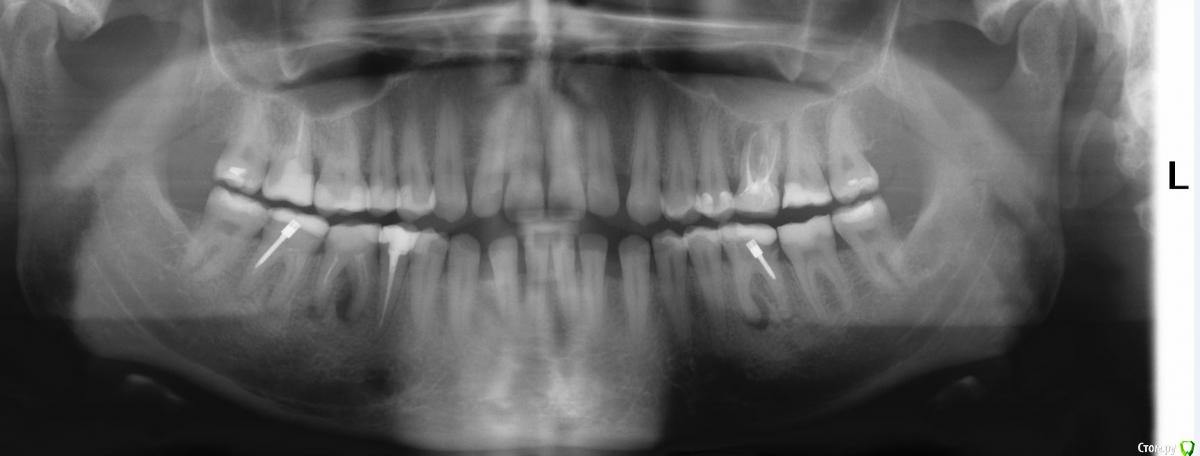

Natalia156 Опубликовано 22 марта, 2018 Поделиться Опубликовано 22 марта, 2018 (изменено) Добрый день! На нижней десне с правой стороны в районе 6го зуба появился бугорок, гноя нет, не болит.Можно ли не удалять зуб? Изменено 22 марта, 2018 пользователем Natalia156 Ссылка на комментарий

red_butler Опубликовано 22 марта, 2018 Поделиться Опубликовано 22 марта, 2018 Я бы не спешил с удалением, если зуб подлежит протезированию, то перелечить каналы и покрыть искусственной коронкой. Практически все Ваши "мертвые" зубы требуют перелечивания Ссылка на комментарий

St. Опубликовано 23 марта, 2018 Поделиться Опубликовано 23 марта, 2018 Можно ли не удалять зуб? Прямых показаний к удалению нет, можно перелечить каналы и восстановить зуб коронкой и потом за ним наблюдать.+1 к необходимости перелечивать планово остальные зубы без нервов с воспалением. Ссылка на комментарий